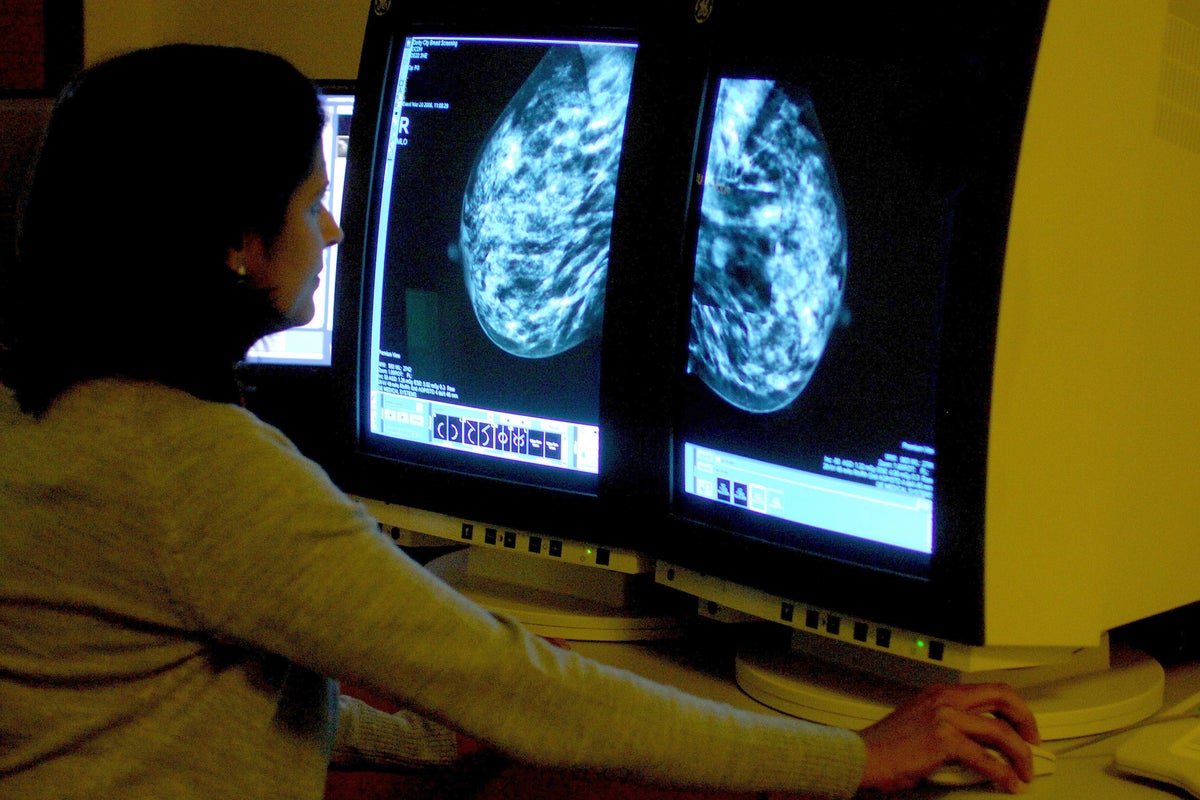

KAT6 Inhibition Shows Path to Overcoming Resistance Mechanisms in ER+ Breast Cancer

Due to its amplification in approximately 12% to 15% of patients with estrogen receptor (ER)–positive breast cancer and ability to repress ER gene transcription, thereby overcoming ESR1-mediated resistance to endocrine therapy, KAT6 had garnered attention …